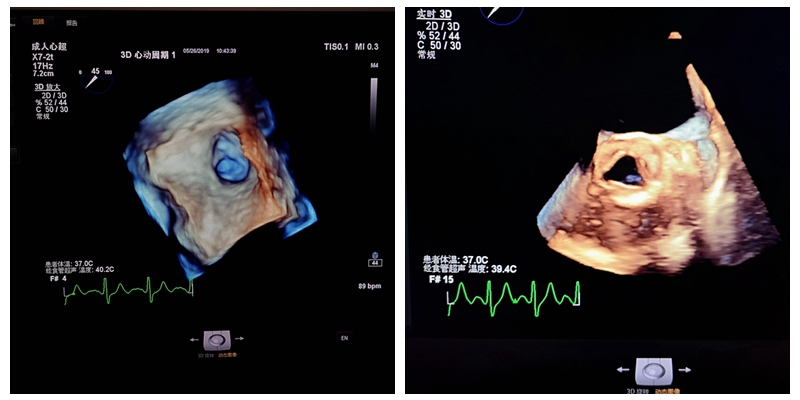

在TEE下,可从多角度、多方位、立体成像实时呈现心脏结构,检查提供左心房增大,同时可以观察左心耳内有无血栓形成,这在经胸部心超检查是很难发展现的。

经食道超声心动图,即食道心脏彩超,就是将超声探头置入食管内,直接贴在心脏的后方,从后向前观察心脏,能充分显示左、右心房、房间隔、心耳、肺静脉和主动脉、各瓣膜的结构等优点,能更加准确地诊断心脏细小病变及疑难疾病。

TEE与普通的经胸超声(TTE)相比,避免了肥胖、胸壁和肺组织的的影响,故可显示出清晰的图像,提高对心血管疾病诊断的敏感性和可靠性,便于进行心脏手术中的超声监测与评价。